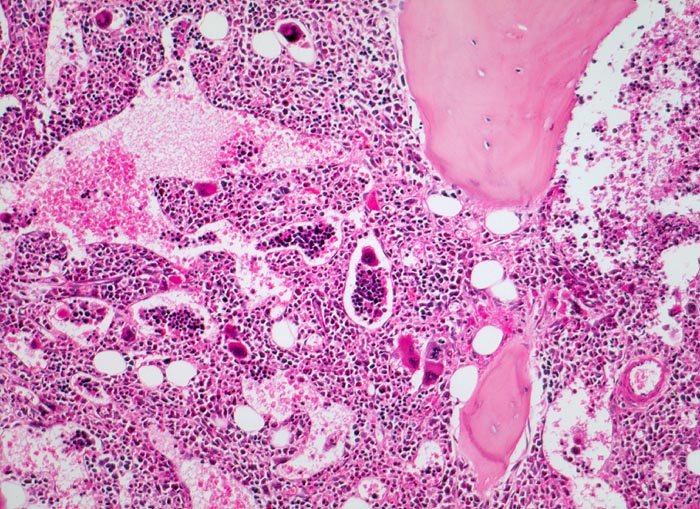

Die Erkrankung ist charakterisiert durch Knochenmarkfibrose, Hepato-Splenomegalie und extramedulläre Blutbildung. Diese findet sich am häufigsten in Leber und Milz, seltener in Lymphknoten, Nieren, Nebennieren, Dura mater, Gastrointestinaltrakt, Lunge, Mamma oder Haut. Blut und Knochenmark sind immer involviert. Die Krankheit entwickelt sich über ein initiales präfibrotisches Stadium mit hyperzellulärem Knochenmark zum fibrotischem Stadium (vorliegendes Präparat). Das fibrotische Stadium ist gekennzeichnet durch eine Vermehrung von Reticulin- und/oder Kollagenfasern und oft einer Knochenneubildung (=Osteomyelosklerose). Die Zellularität des Knochenmarks ist dann vermindert und dilatierte Marksinus enthalten intraluminale Blutbildungsherde. Es besteht eine auffallende Proliferation von Gruppen bildenden atypischen Megakaryozyten.

- Osteosklerose: verplumpte und breite Knochenbälkchen.

- Kollagenfibrose.

- Dilatierte Sinusoide mit intrasinusoidaler Blutbildung.

- Vermehrung von atypischen, in Gruppen liegenden Megakaryozyten mit abnorm lobulierten Kernen.

- Nacktkernige (zytoplasmaarme) und vergrösserte Megakaryozyten.